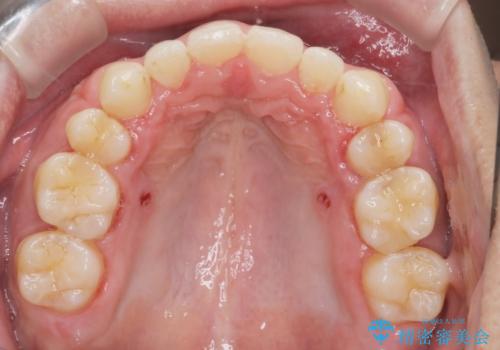

前歯の隙間を閉じたい 口元も下げたい ハーフリンガルによる抜歯矯正

上顎正中離開と、口唇の突出感がありました。

上下左右の歯を1本ずつ抜歯しして、上顎の前歯を後方に移動させるのと、正中の隙間を閉じる計画としました。

抜歯をせず上顎の正中離開のみの矯正もできましたが、患者様と相談して口元の改善も同時に行うために抜歯矯正の計画としました。